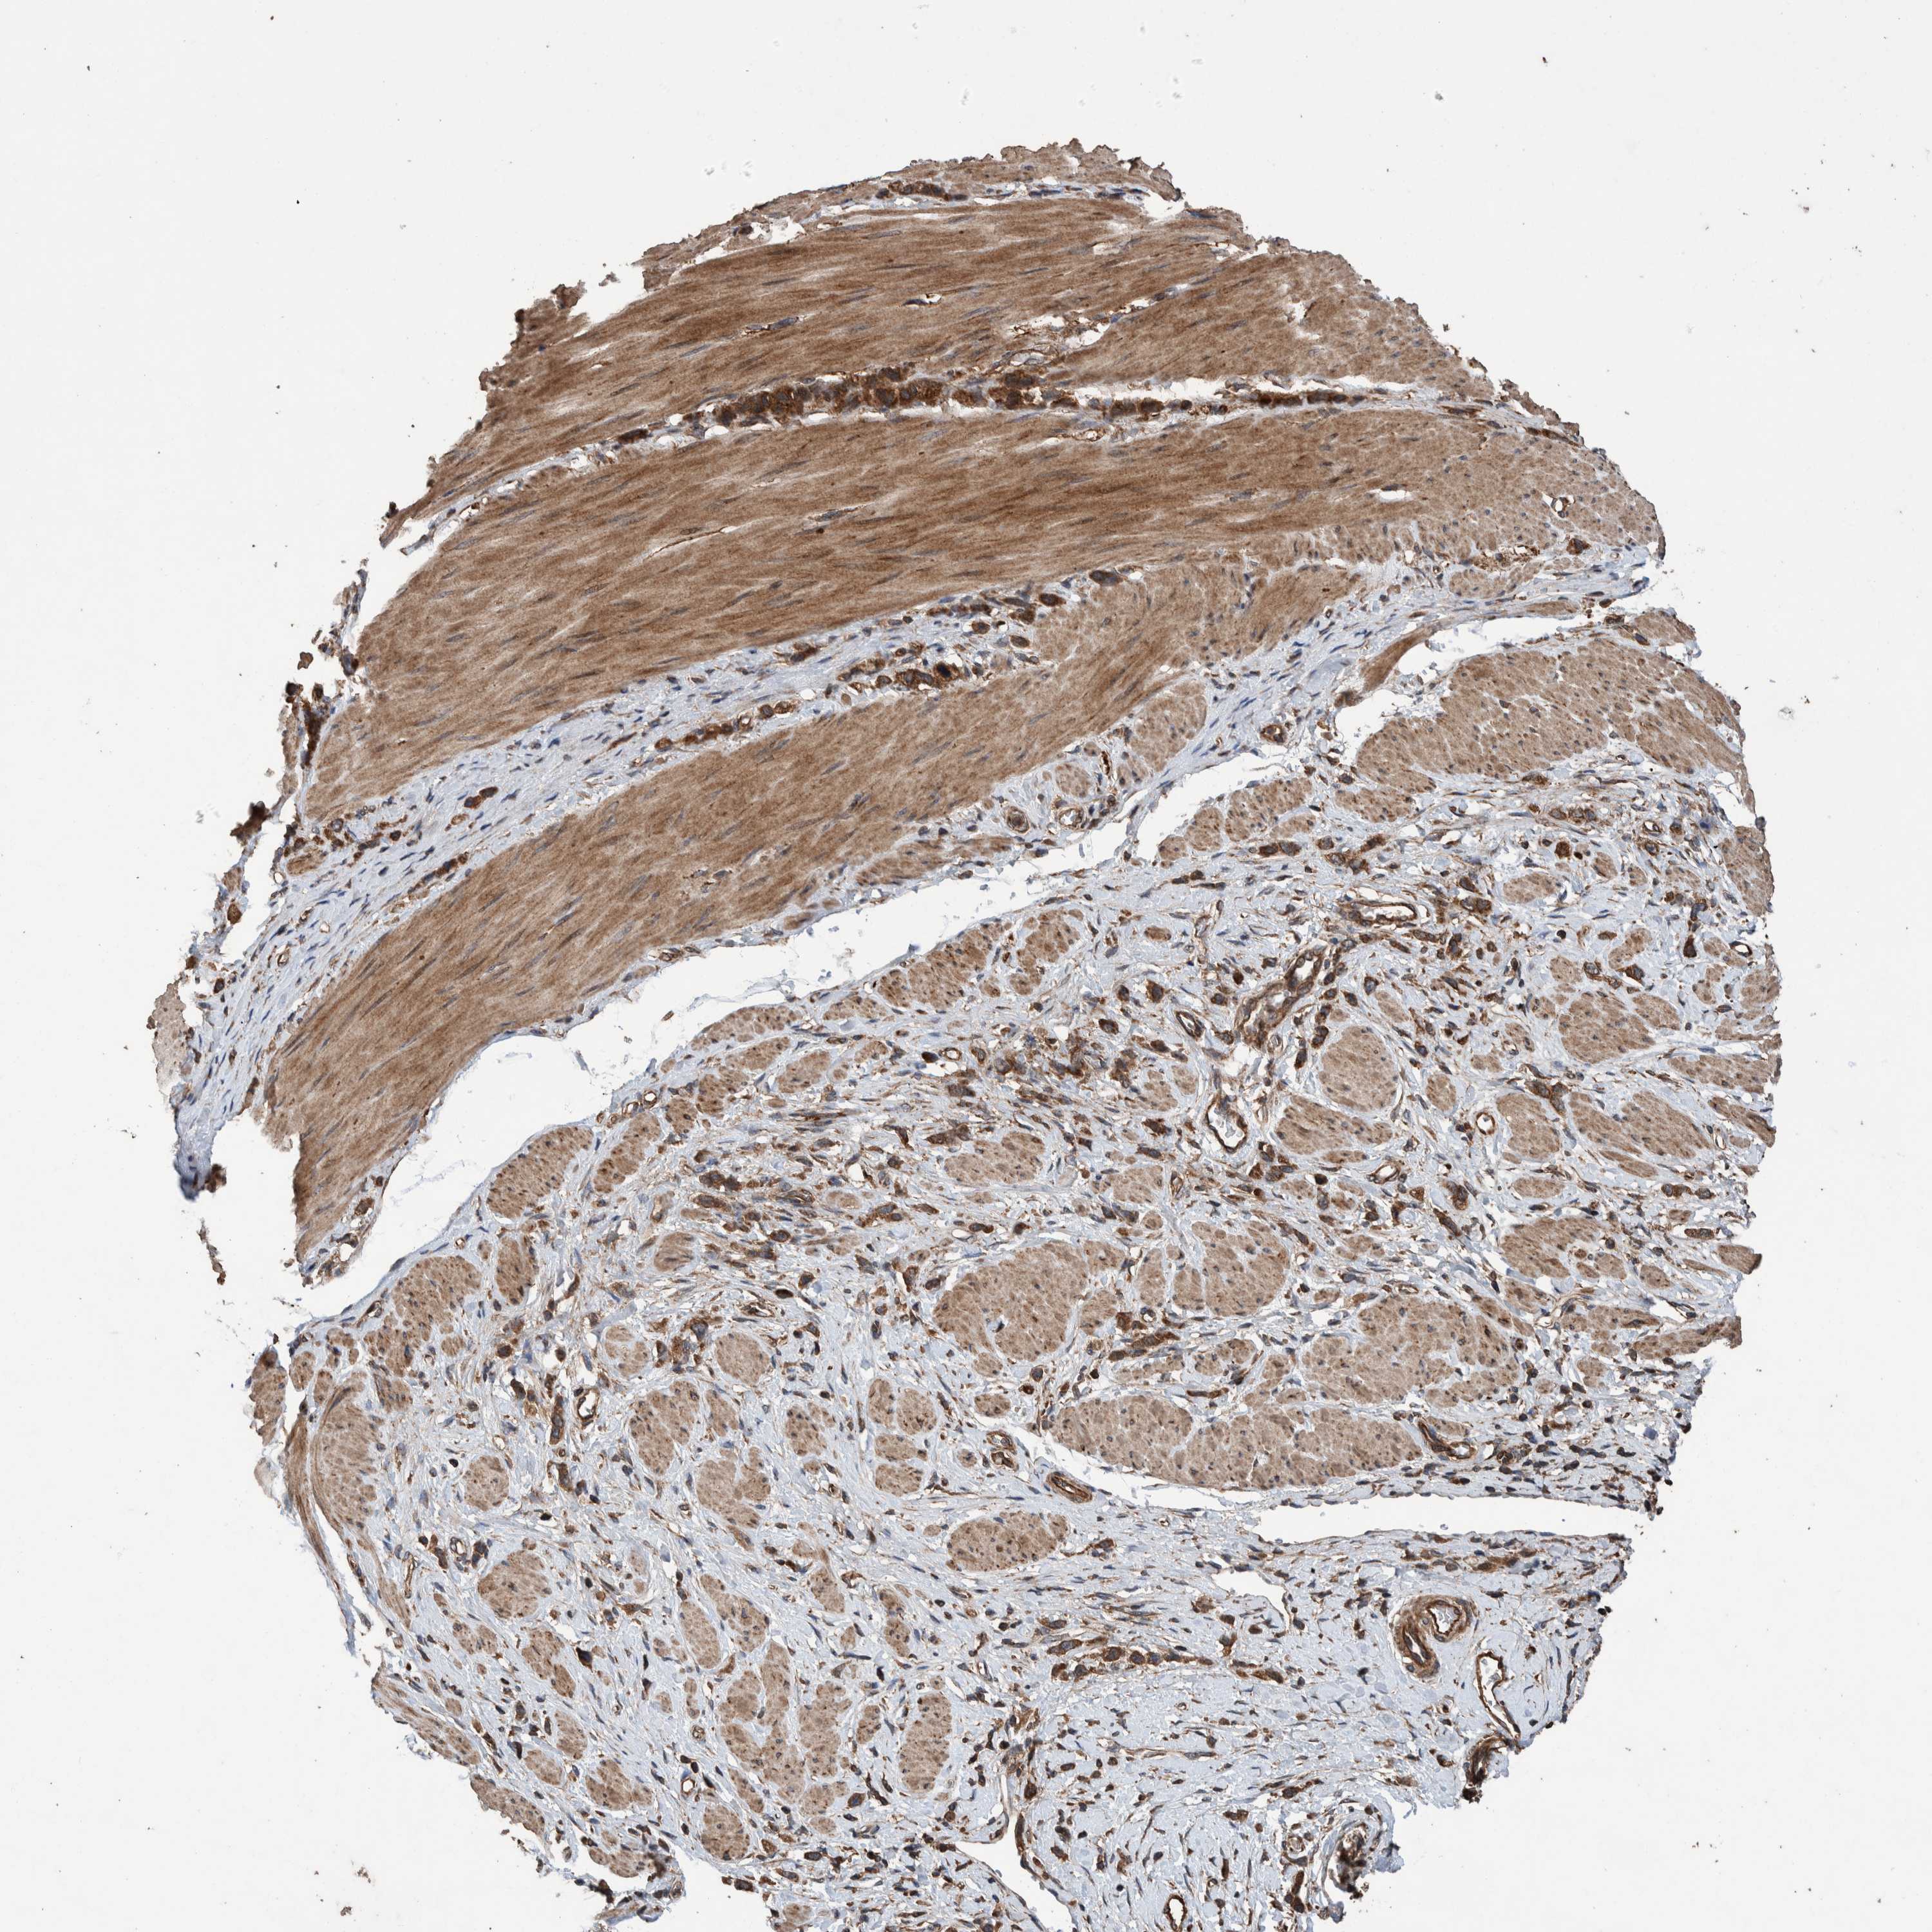

STOMACH CANCER - Protein expressioni

A mouse-over function shows sample information and annotation data. Click on an image to view it in a full screen mode. Samples can be filtered based on level of antibody staining by selecting one or several of the following categories: high, medium, low and not detected. The assay and annotation is described here.

Antibody stainingi

Antibody staining in the annotated cell types in the current human tissue is reported as not detected, low, medium, or high, based on conventional immunohistochemistry profiling in selected tissues. This score is based on the combination of the staining intensity and fraction of stained cells.

Each image is clickable and will lead to virtual microscopy that enables deeper exploration of all samples and also displays staining intensity scores, fraction scores and subcellular localization as well as patient and tissue information for each sample.

Antibody HPA023623

Antibody HPA066431

Staining

High

Medium

Low

Not detected

Intensity

Strong

Moderate

Weak

Negative

Quantity

>75%

75%-25%

<25%

None

Location

Nuclear

Cytoplasmic/membranous

Cytoplasmic/membranous,nuclear

Adenocarcinoma, NOS

Adenocarcinoma, High grade